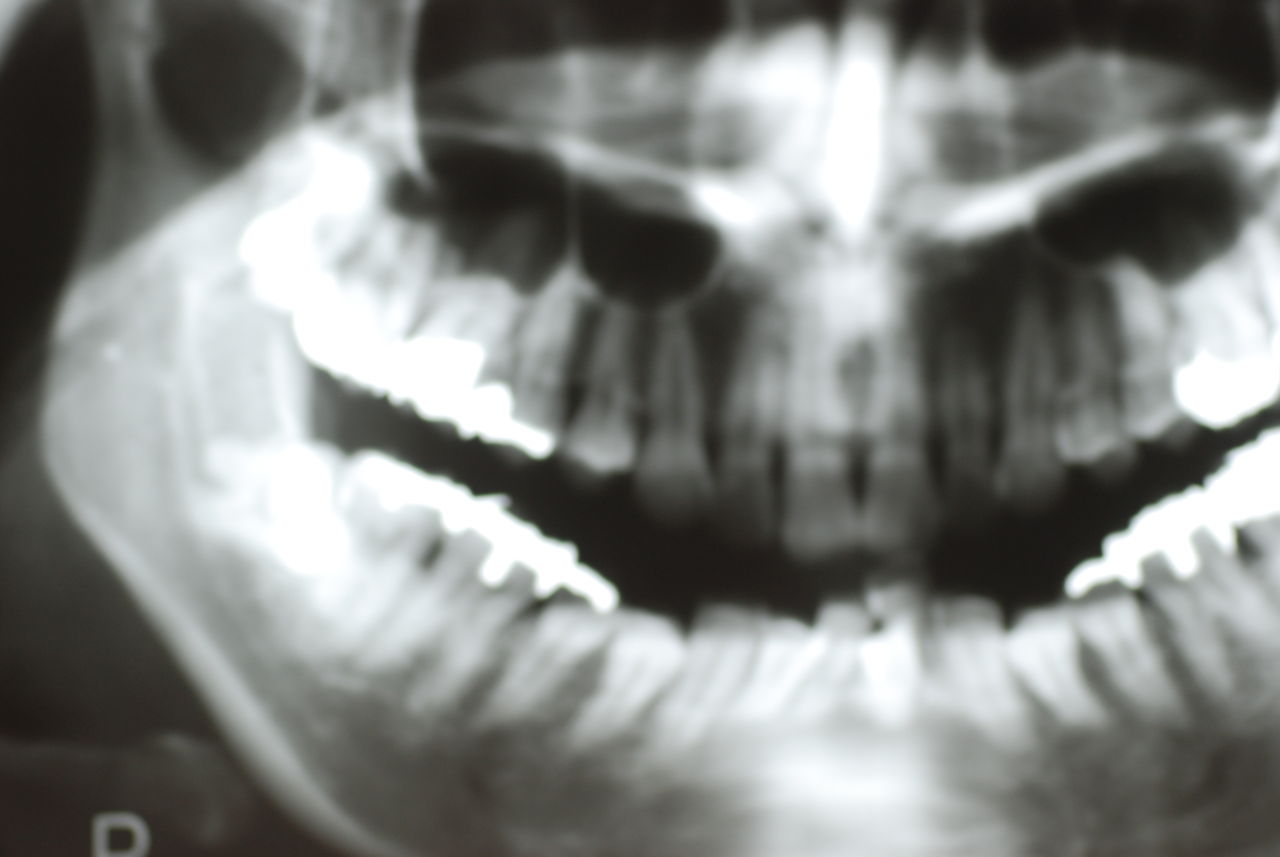

平成9年治療、虫歯と神経の処置、歯周病の治療

![a7fa4f9f-s[1]](https://livedoor.blogimg.jp/netdental/imgs/4/2/42470ffa.jpg)

2012,7月来院

欠けたところを埋めておしまいです。